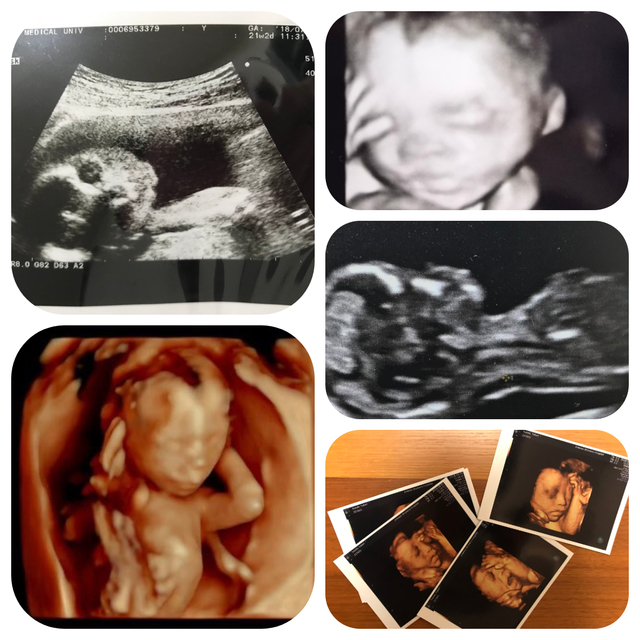

エコー写真撮影時のエピソード(妊娠16週目:16w0d)

まさかの足での敬礼。産婦人科の先生も、足で敬礼してる子はなかなかいないねって笑ってました。もっと前に撮ったエコーではここまで顔立ちハッキリしてなくわからなかったですが、、この時のエコーは鼻と口元が主人にそっくりでびっくり。主人に「似てるね」って話したら、「そうかなぁ?」って照れながら喜んでました。

エコー写真で見るとご主人に似ているとのことで、ますます将来が楽しみですね!